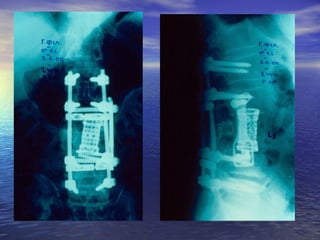

ΘΘωωρραακκοο –– οοσσφφυυϊϊκκάά

κκααττάάγγμμαατταα ΘΘ1111--ΟΟ11

• ααππόό ββίίααιιηη υυππέέρρκκααμμψψηη κκααιι σσττρροοφφήή

• εείίννααιι σσυυννήήθθωωςς αασσττααθθήή ((εευυάάλλωωττοοιι οοιι αασσθθεεννεείίςς

σσττιιςς σσττρροοφφιικκέέςς κκιιννήήσσεειιςς))

• ππττώώσσηη ααππόό ύύψψοοςς,, ττρροοχχααίίοο ααττύύχχηημμαα,,

δδιιααττιιττρρααίίννοονν ττρρααύύμμαα

• σσυυννοοδδεεύύοοννττααιι ααππόό κκαακκώώσσεειιςς σσππλλάάχχννωωνν

((ήήππααττοοςς,, σσππλληηννόόςς,, εεννττέέρροουυ,, κκοοιιλλιιώώνν,,

ααγγγγεείίωωνν)) ρρήήξξηη δδιιααφφρράάγγμμααττοοςς

ΘΘωωρραακκοο –– οοσσφφυυϊϊκκάά κκααττάάγγμμαατταα ΘΘ1111--ΟΟ11 • ααππόό ββίίααιιηη υυππέέρρκκααμμψψηη κκααιι σσττρροοφφήή • εείίννααιι σσυυννήήθθωωςς αασσττααθθήή ((εευυάάλλωωττοοιι οοιι αασσθθεεννεείίςς σσττιιςς σσττρροοφφιικκέέςς κκιιννήήσσεειιςς)) • ππττώώσσηη ααππόό ύύψψοοςς,, ττρροοχχααίίοο ααττύύχχηημμαα,, δδιιααττιιττρρααίίννοονν ττρρααύύμμαα • σσυυννοοδδεεύύοοννττααιι ααππόό κκαακκώώσσεειιςς σσππλλάάχχννωωνν ((ήήππααττοοςς,, σσππλληηννόόςς,, εεννττέέρροουυ,, κκοοιιλλιιώώνν,, ααγγγγεείίωωνν)) ρρήήξξηη δδιιααφφρράάγγμμααττοοςς